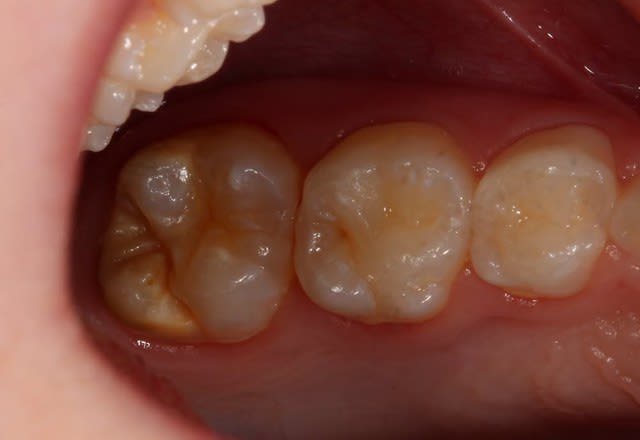

Je vois une petite fille de 9 ans présentant des MIH sur les 4 premières molaires.

Rien sur les incisives, OUF!

La 46 est très atteinte, mais pas de symptomatologie!

Molar Incisor Hypomineralization : taches opaques blanc-jaune de l'émail des premières molaires permanentes (et dans 3 cas sur 4 des incisives permanentes). L'émail est fragile est tend à se fracturer sous l'effet des pressions occlusales, majoritairement durant les deux années suivant l'éruption.

Une fois l'émail fracturé, la dentine sous-jacente n'est plus protégée (carie, pulpopathies).

Tant que tu n'as pas d'émail fracturé, il n'y a pas nécessité d'intervention invasive : contrôle/fluoration tous les 6 mois de 6 à 10 ans et sealants.

Après 10 ans, si tu n'as pas eu de fracture, il est probable qu'il n'y en aura jamais de majeure : surveillance annuelle.

Si le délabrement est trop important, alors une coiffe pédo semble l'indication idéale.

Une fluoration ? Ok sur petite atteinte, mais ici, la mih parait déjà très avancée.

Une extraction? Ok sur une atteinte très importante des 4 molaires.

l'avantage de la coiffe pédo est que le délabrement est vraiment minime car la surface occlusale est déjà délabrée. Il sera toutefois nécessaire de coiffer définitivement en denture définitive après l'orthodontie.